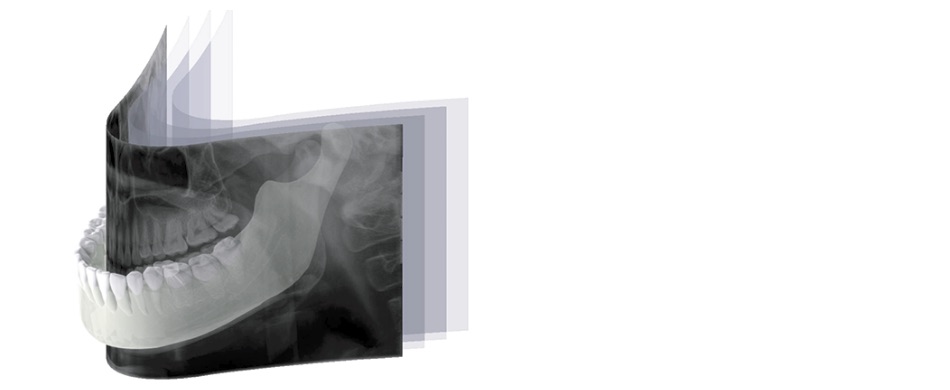

「オートフォーカス」はパノラマモード専用の機能です。焦点が合う最適な部分を自動で抽出して画像を生成します。位置付けの失敗による再撮影のリスクも軽減されます。